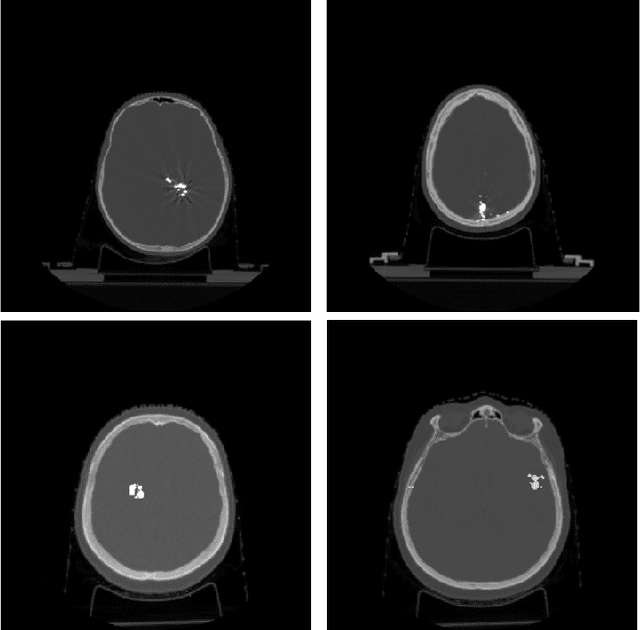

Abstract:Target imbalance affects the performance of recent deep learning methods in many medical image segmentation tasks. It is a twofold problem: class imbalance - positive class (lesion) size compared to negative class (non-lesion) size; lesion size imbalance - large lesions overshadows small ones (in the case of multiple lesions per image). While the former was addressed in multiple works, the latter lacks investigation. We propose a loss reweighting approach to increase the ability of the network to detect small lesions. During the learning process, we assign a weight to every image voxel. The assigned weights are inversely proportional to the lesion volume, thus smaller lesions get larger weights. We report the benefit from our method for well-known loss functions, including Dice Loss, Focal Loss, and Asymmetric Similarity Loss. Additionally, we compare our results with other reweighting techniques: Weighted Cross-Entropy and Generalized Dice Loss. Our experiments show that inverse weighting considerably increases the detection quality, while preserves the delineation quality on a state-of-the-art level. We publish a complete experimental pipeline for two publicly available datasets of CT images: LiTS and LUNA16 (https://github.com/neuro-ml/inverse_weighting). We also show results on a private database of MR images for the task of multiple brain metastases delineation.

Abstract:Recent CT Metal Artifacts Reduction (MAR) methods are often based on image-to-image convolutional neural networks for adjustment of corrupted sinograms or images themselves. In this paper, we are exploring the capabilities of a multi-domain method which consists of both sinogram correction (projection domain step) and restored image correction (image-domain step). Moreover, we propose a formulation of the first step problem as sinogram inpainting which allows us to use methods of this specific field such as partial convolutions. The proposed method allows to achieve state-of-the-art (-75% MSE) improvement in comparison with a classic benchmark - Li-MAR.

Abstract:Deep learning methods are actively used for brain lesion segmentation. One of the most popular models is DeepMedic, which was developed for segmentation of relatively large lesions like glioma and ischemic stroke. In our work, we consider segmentation of brain tumors appropriate to stereotactic radiosurgery which limits typical lesion sizes. These differences in target volumes lead to a large number of false negatives (especially for small lesions) as well as to an increased number of false positives for DeepMedic. We propose a new patch-sampling procedure to increase network performance for small lesions. We used a 6-year dataset from a stereotactic radiosurgery center. To evaluate our approach, we conducted experiments with the three most frequent brain tumors: metastasis, meningioma, schwannoma. In addition to cross-validation, we estimated quality on a hold-out test set which was collected several years later than the train one. The experimental results show solid improvements in both cases.